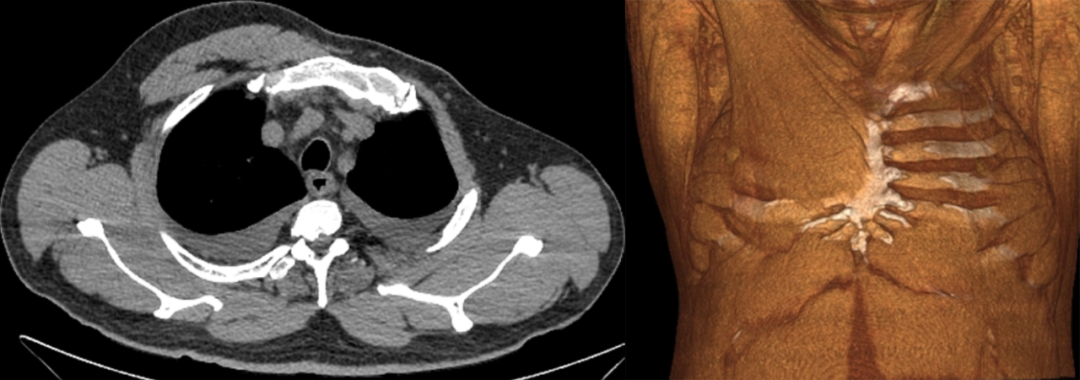

男,39 岁,体检肺 CT。

影像表现:右侧胸大肌及胸小肌缺如。

最终诊断为:部分型 Poland 综合征 (Poland syndrome)

影像学:主要表现为胸壁、肌肉、乳房及同侧上肢缺损或畸形的程度,并与健侧对比。3D 重建有利于更明确显示胸廓、肋骨及软组织畸形,本例右侧胸大肌及胸小肌缺如。